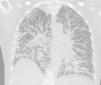

We describe below the case of a female patient, 65 years of age, history of COPD, former smoker, who reported a 6-month history of progressive dyspnea, with no other associated symptoms. On physical examination, she had dry crackles in both lung bases. Complete blood count and biochemistry were normal. An echocardiogram was performed, which was normal. Spirometry revealed a severe obstructive defect (FEV1 47%) with moderate restriction (FVC 61%). Diffusing capacity for CO was severely reduced (17%). The 6-min walk test showed a significant drop in oxygen saturation and had to be suspended due to significant dyspnea and O2 saturation of 73%. A chest computed tomography (CT) was performed that showed multiple nodular images, mostly densely calcified, with thickening of interlobular septa, mainly peripheral and in the basal segments (Fig. 1). A lung biopsy, performed by video-assisted thoracoscopy, showed the presence of nodular foci of osseous metaplasia.

High-resolution CT shows reticulonodular opacities, septal thickening, and less frequently, ground glass opacification, bronchiectasis, and honeycombing.5